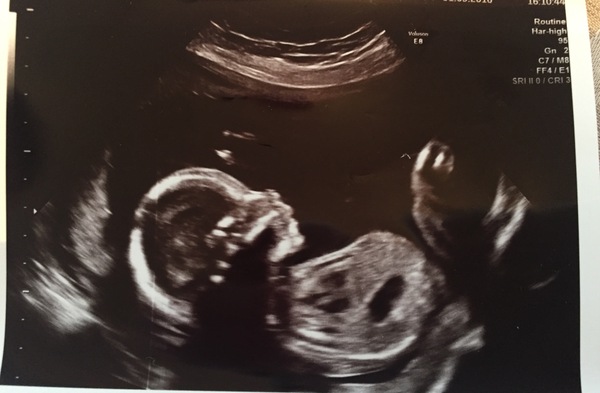

Yes me Northern, I've got anterior placenta had my 20 week scan on Thursday - we're having a boy! And he did not stop moving, but I couldn't feel a thing! There were arms and legs going everywhere and he was twisting and turning the whole time but I couldn't feel it!

I've felt a few things over the weekend but because it's so quick and faint it's hard to catch it, I can't wait until I feel proper kicks! I'm 21 weeks tomorrow

Glad it's not just me - 20 week scan showed loads of movement but nothing yet!

We had our 20 week scan today, which all went well! Lots of wriggling, which my DH has finally seen too, which is so lovely. Now we'll start to seriously look at buying things!

Glad to see scans all going well. I had mine yesterday too and was lovely to see baby wriggling around. I had to roll around quite a bit in order for them to get all the measurements they needed as baby kept chasing away. We didn't want to know the gender and before the scan I was worried I might see something to give it away but there was no telling as baby was wriggling so much and had either legs crossed or in the air!